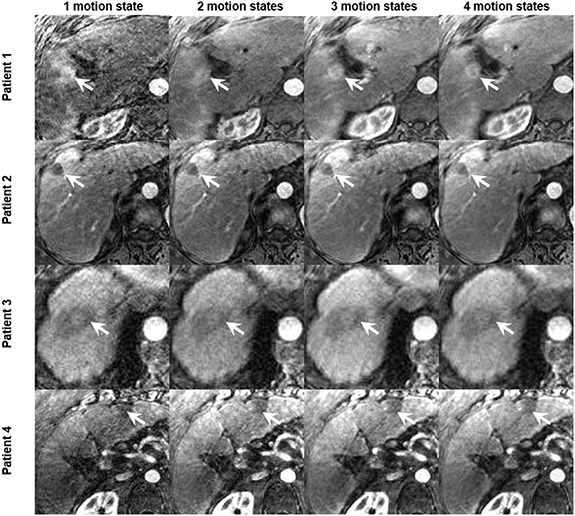

XD-GRASP reconstructed with increased motion states with different number of spokes improves the contrast-to-noise ratio and the signal-to-noise ratio (p < 0.05) but reduces temporal resolution (0.04 volume/s vs 0.17 volume/s for one motion state) (p < 0.05) (figure 6). XD-GRASP with 3 and 4 motion states had higher overall image quality scores compared to XD-GRASP with 1 and 2 motion states as it showed reduced streak artefact (figure 8). Results for image reconstructed with different number of spokes show that on average, the reconstruction with 4 phases received the higher scores (4.6) while the reconstruction with one phase received the lower one (1).

Figure 8. Example of reconstructed XD-GRASP images for four patients with increasing number of motion states with multiple number of spokes (tumors identified by white arrow).

Standard image High-resolution imageFigure 6 shows that increasing the number of respiratory motion states improves the SNR and CNR but reduce the temporal resolution thus influencing quantitative parameters that capture rapid signal changes. This is confirmed with figure 8, which clearly shows the improvements of the image quality by increasing the number of motion states for several patients.